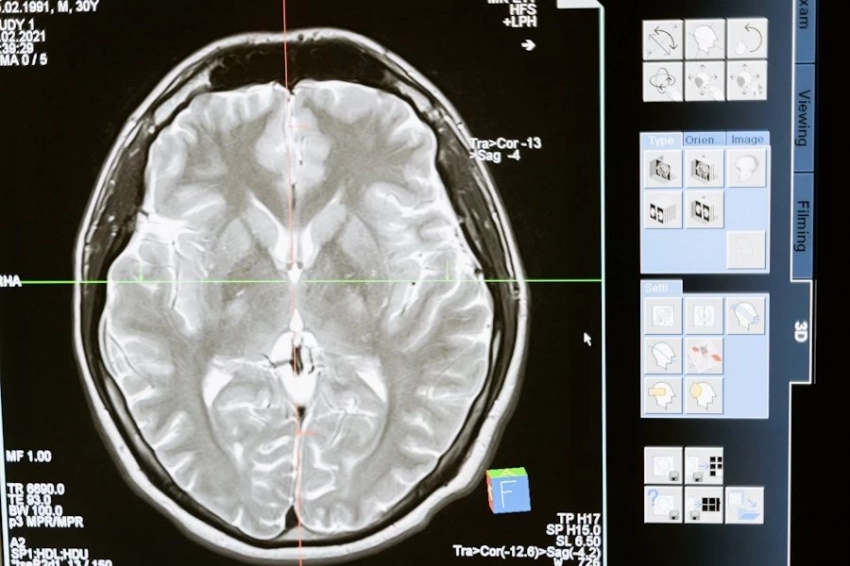

Фото из открытых источников 63-летняя Бет Роджерс из американского города Хейзен стала первым человеком в США, прошедшим экспериментальное лечение опухоли мозга с использованием вируса простуды. Уникальную операцию провели нейрохирурги Университета медицинских наук Арканзаса (UAMS), внедрив в опухоль аденовирус, который...